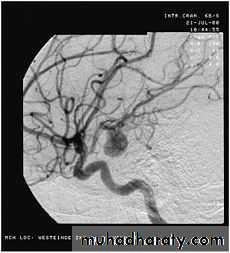

• Angiography

Angiography: